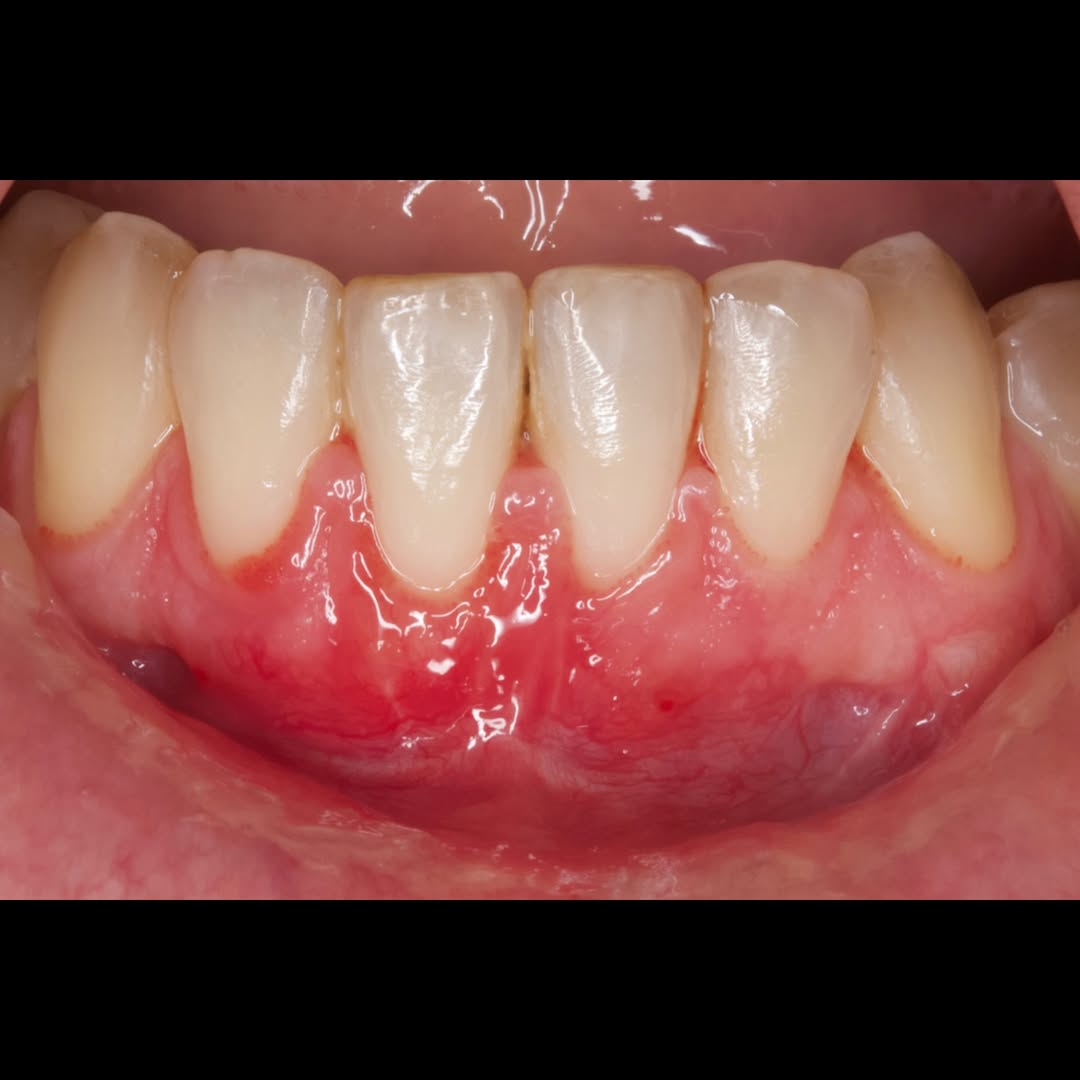

Se presenta un caso clínico de restauración directa en resina composite, ejemplo del valor de la precisión y la técnica meticulosa incluso en procedimientos considerados rutinarios dentro de la práctica diaria. El caso pone en evidencia la importancia del control de la morfología, la textura y la integración cromática, así como del adecuado aislamiento del campo operatorio y la estratificación del material, factores determinantes para conseguir un resultado natural, funcional y duradero. A través de una ejecución cuidadosa, se logró una restauración estéticamente imperceptible y funcionalmente estable, que respeta los principios de mínima invasión y adhesión efectiva. Este tipo de procedimientos, aunque cotidianos, reflejan la constancia y el nivel de exigencia clínica necesarios para ofrecer odontología de calidad en todos los casos, independientemente de su complejidad.